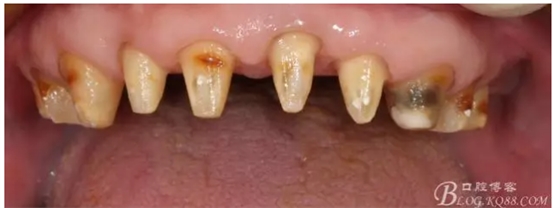

早期的病歷大約在2009年左右,那時(shí)只做了下頜的套筒冠

當(dāng)時(shí)勸病人上頜也做了修復(fù),但是病人感覺(jué)這樣還可以,把下面牙齒鑲好再說(shuō),雖然上面的牙齒不同程度的牙齦萎縮,都有些松動(dòng),但是患者年歲已高,只做下頜修復(fù)。囑咐病人半年復(fù)診一次,可是病人這一走就是2年,來(lái)要求制作上牙的修復(fù)

上牙出現(xiàn)了不同程度的牙齦萎縮